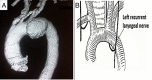

(A) MDCT aortogram showing a 6 cm×5 cm saccular aneurysm from the inferolateral wall of the aortic arch, flush with the origin of the left subclavian artery. The aneurysm is seen to bulge inferiorly towards the origin of ligamentum arteriosum. (B) Schematic representation of the course of the left recurrent laryngeal nerve and the mechanism of cardiovocal syndrome. The nerve hooks around the aortic arch directly opposite to the ostium of the left subclavian artery, corresponding to the anatomical site of the ligamentum arteriosum.